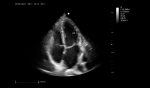

Excelentes imágenes clínicas

|

|

|

|

|

|